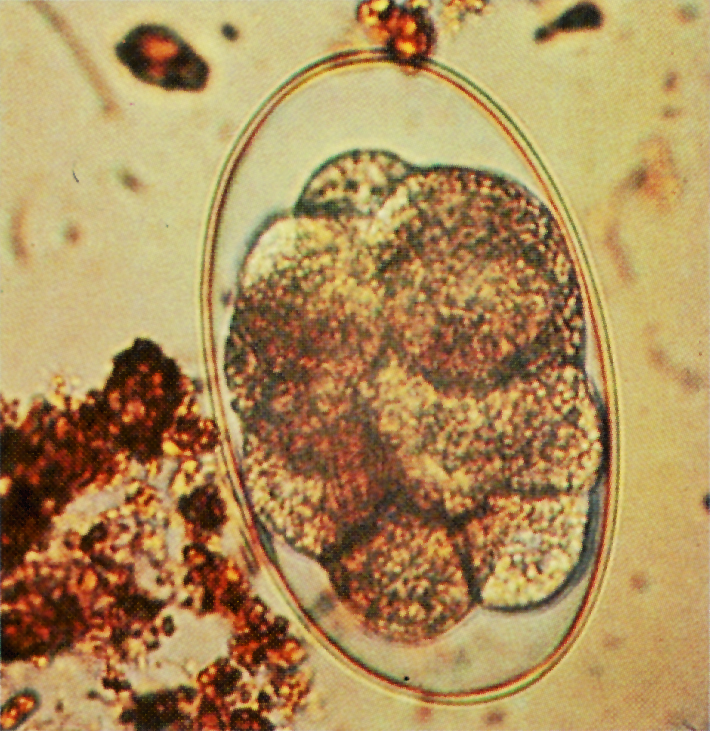

When your horse swallows the tiny small strongyle larvae, those larvae burrow into the wall of the large intestine where they're surrounded a thick-walled cyst. Larvae are quite adaptive and can go on to develop as adult worms or remain in this protected encysted stage from two to three months all the way up to three years.

When this happens, encysted larvae emerge from the intestinal wall and migrate to the large colon where they continue developing. Once mature, the adults lay eggs, which are passed in the horse's manure and the cycle continues as these eggs develop into infective larvae in the grass to be picked up by the same horse or other horses.